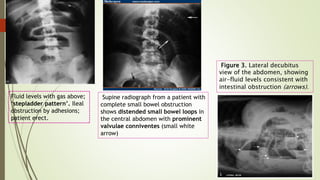

 In small bowel

 Central 3cm thick

diameter

 Vulvulae coniventae

 Ileum may occur

tubeless

 In large bowel

 Peripheral diameter 6cm

 Presence of haustration

Fluid levels with gas above;

‘stepladder pattern’. Ileal

obstruction by adhesions;

patient erect.

Supine radiograph from a patient with

complete small bowel obstruction

shows distended small bowel loops in

the central abdomen with prominent

valvulae conniventes (small white

arrow)

Figure 3. Lateral decubitus

view of the abdomen, showing

air-fluid levels consistent with

intestinal obstruction (arrows).